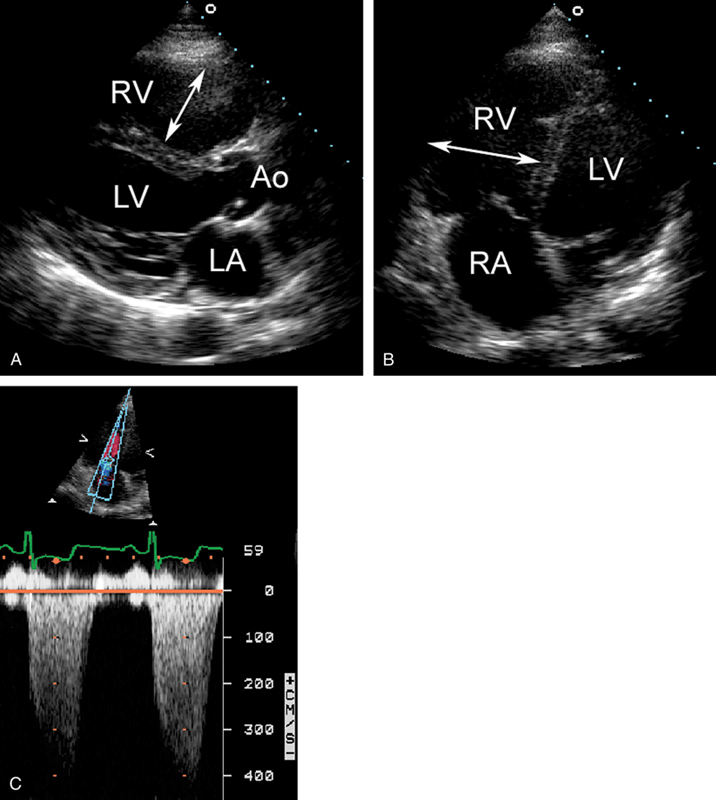

فحوصات تشخيصية لبعض امراض القلب والشرايين التاجية